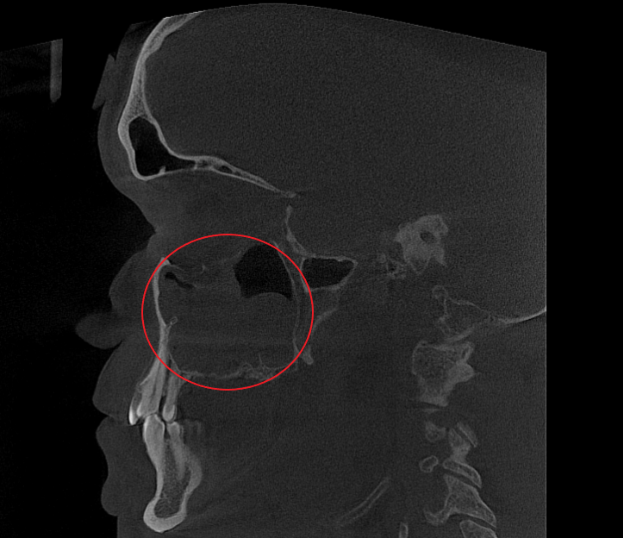

- Компьютерная томография (КЛКТ) околоносовых пазух и височных костей: Этот высокоинформативный метод диагностики объективно показал искривление носовой перегородки вправо, субтотальное снижение пневматизации (воздушности) левой верхнечелюстной пазухи, что свидетельствовало о хроническом воспалительном процессе. Костно-деструктивных изменений не выявлено.

- Хронический левосторонний верхнечелюстной синусит (J32.0). Длительное воспаление слизистой оболочки левой гайморовой пазухи, подтвержденное КТ.

Послеоперационный период протекал гладко. Проводились регулярные туалеты полости носа, промывание оперированной пазухи, назначались средства для увлажнения и регенерации слизистой оболочки, а также местная антибактериальная терапия. По результатам оперативного лечения носовое дыхание было полностью восстановлено, признаки активного воспаления купированы. Спустя 1.5 месяца после проведенного оперативного лечения проведено КТ околоносовых пазух в динамике, что отражает промежуточный результат оперативного лечения. На снимках: Перегородка носа располагается по центру, оперативно созданное соустье левой верхнечелюстной пазухи функционирует, пневматизация левой верхнечелюстной пазухи значительно улучшилась. Окончательный результат можно будет оценить через 3 месяца после проведенной операции, и при полной пневматизации левой верхнечелюстной пазухи пациент сможет приступить к установке зубных имплантов в верхнюю челюсть слева.